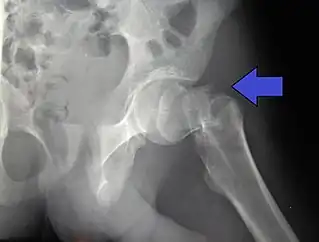

![]() Fractura intertrocantérica en un masculino de 17 años de edad. | ||